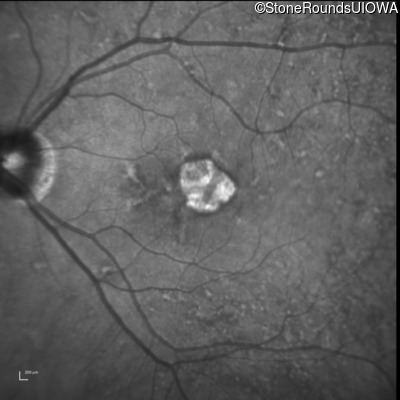

Infrared Fundus Photograph - Left - 20/40 +1

Exemplar